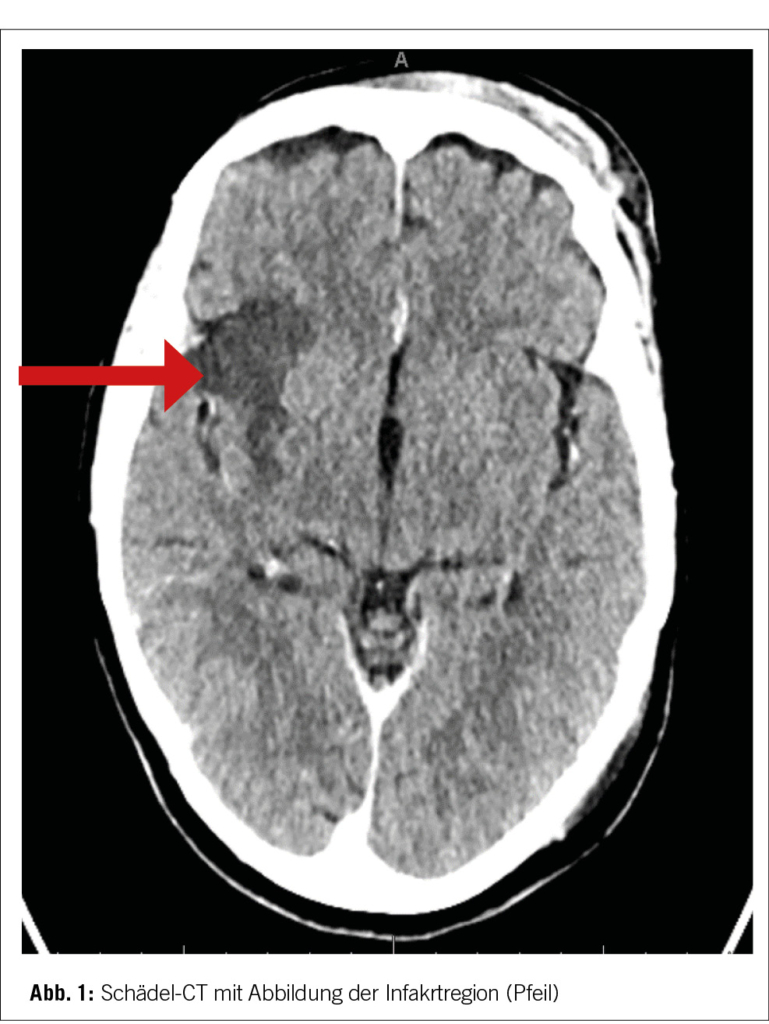

Dort erfolgte eine komplikationslose mechanische Thrombendarteriektomie und das Gefäss konnte mittels Stentretriever und Thrombo-Aspiration wiedereröffnet werden. Das Aspirat wurde anschliessend zur histopathologischen Untersuchung abgeschickt. Postinterventionell erfolgte das Standard-Post-Stroke Work-Up mittels Langzeit-EKG, Duplexsonographie der Halsgefässe und TTE. In den durchgeführten Untersuchungen liess sich initial keine Strokeursache eruieren. Im Verlauf kam das Ergebnis der Histopathologie des aspirierten Thrombus, an. Es konnten dabei im Thrombus papillär ausgebaute Gewebsfragmente mit fibroelastischen Kernstücken und wenig myxoiden Anteilen, welche an eine Embolie eines papillären Fibroelastoms denken liessen, nachgewiesen werden (Bild 2).

Die typischen neurologischen Ausfälle, mit welchen sich die Patientin initial auf dem Notfall vorstellte, führten zu einer gezielten Bildgebung mittels Schädel CT-Angiographie, wo der Hirninfarkt im rechten Mediastromgebiet, dargestellt werden konnte. Die initialen Abklärungen mittels TTE, Carotis-Sonographie und Herzrhythmusüberwachung, lieferten zunächst keine Ätiologie. Es wurde der Entscheid zur mechanischen Thrombendarteriektomie getroffen, wobei sich letztendlich erst im Thrombusaspirat histopathologisch ein papilläres Fibroelastom, als primäre kardiale Emboliequelle des Schlaganfalls, darstellen liess und die Stroke-Ursache somit geklärt werden konnte.

Zudem lag der histopathologische Befund des Thrombusaspirates vor, welcher ein papilläres Fibroelastom, bestätigte. Eine definitive Sicherheit in der Diagnosestellung, erlangt man letztendlich jedoch nur mittels einer kardiochirurgischen Exzision.